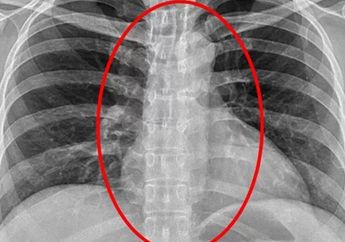

INFOGRAFIS : Waspada, Jangan Anggap Sepele Gangguan Nafas Saat Tidur, Dampaknya Bisa Sampai Stroke

8 Tahun yang lalu - Normalnya selama tidur oksigen mengalir melalui tenggorokan masuk dan keluar ke paru - paru dengan ritme yang teratur. Sleep apnea merupakan gangguan pernafasan saat tidur.